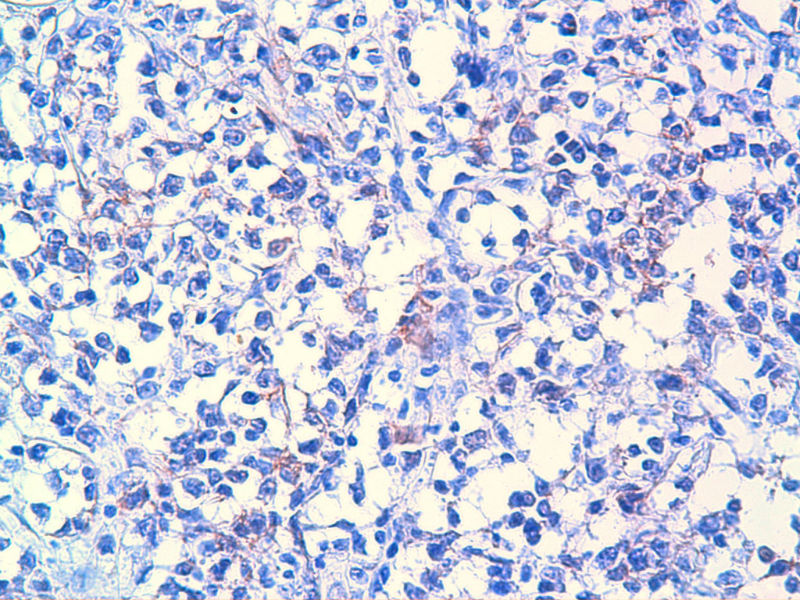

免疫组化染色:CA125(-),PLAP(-),NSE灶状阳性,Vimentin(+),a-inhibin(-),CK7(-),CK20(-),CD15(-),PSA(-),S100(-),MyoD1(-),CD38(-),CD56(-),HMB45(-),CK8(-),NF(-),CGA(-),syn(+),MPO散在(+)可能是炎细胞吧,LCA(+),CD133(+).

是的,syn(+),LCA(+), CD79a阳性, CD3阴性,NSE是局部胞核,胞浆着色,主要是胞浆着色;SYN也是局部,主要是胞核着色,胞浆很少。不对吗?我也迷糊。也许我看错了,不像那种典型的胞浆颗粒状着色。大家帮看一看。

今天又做了免疫组化,请大家帮看看。CD10(-),CD138(-),CDX2(-),CD3(-),CyclinD1(-),CD2(-),CD117(-),CD7(-),CD30(-),CD23(-);CD20强(+),BCL-2,Bcl-6,EMA,PAX-5,MUM-1,CD5,ALK,CD68都是散在阳性,大家帮确定一下是否阳性。B细胞淋巴瘤可以确定了,不知是哪种类型的?